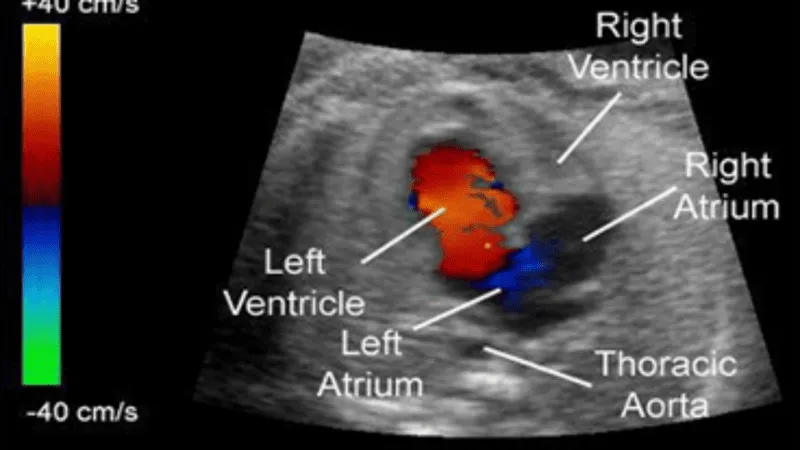

The Pediatrics 2D Echo Color Doppler is a sophisticated imaging tool used to evaluate the cardiovascular system in children. It combines two-dimensional echocardiography with color Doppler technology to provide detailed images and real-time assessments of heart structures and blood flow. The 2D Echo component delivers cross-sectional views of the heart, enabling the examination of its chambers, valves, and walls, while the Color Doppler feature visualizes blood flow and detects any abnormalities or inefficiencies in circulation. This non-invasive and accurate tool is crucial for diagnosing and monitoring congenital heart defects, valve disorders, and other cardiovascular issues in pediatric patients, ensuring timely and effective treatment.